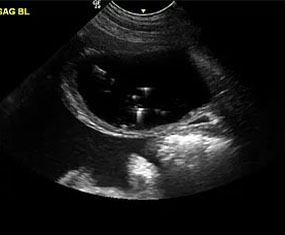

We elected to offer not only abdominal, cardiac and small parts ultrasound but also provide interventional procedures necessary to fulfill the diagnostic pathway. By doing so, we are capable of scanning a patient, working with attending veterinarians to assess patients for biopsy or aspiration and then collecting any samples that may be required to accurately diagnose and address the underlying concern.

At RVUS we have chosen industry leading equipment from vendors with reputable and proven track records in the industry. From the front lines to your final report it is imperative that the equipment and the user provide images that equip the specialists with the highest level of quality and reproducibility to confidently provide an accurate interpretation of the sonogram.

This, in turn, provides you with additional tools to arrive at a diagnosis and prognosis and to enhance the care model for your patient and confidence with your client. Our team of professionals with decades of ultrasound experience encourage the use of ultrasound as a leading route to non-invasively assess organs and pathology in question. To cover that spectrum, a variety of transducers are essential, all with different characteristics.

Whether your patient is 100 lbs or 10 lbs, take comfort in knowing your sonographer is capable of generating images that are sensitive and specific to the clinical concerns.